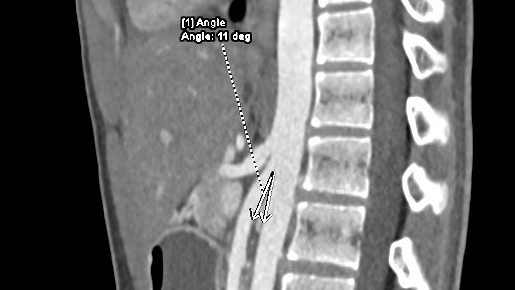

Hội chứng động mạch mạc treo tràng trên hiếm gặp

Hội chứng động mạch mạc treo tràng trên (Wilkie) rất hiếm gặp, chỉ xuất hiện khoảng ở 0,013-0,3% dân số là bệnh lý khó chẩn đoán, dễ bị nhầm lẫn với các bệnh lý khác như viêm tụy, viêm loét dạ dày, khó tiêu chức năng.